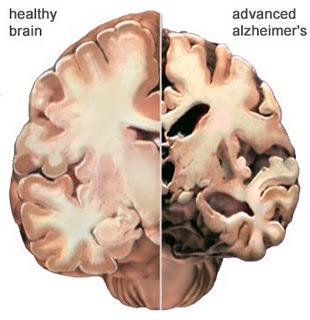

Aunque el origen de la EA no es bien conocido, las lesiones cerebrales que caracterizan el diagnòstico de enfermedad de alzheimer se producen por el acùmulo de una proteìna denominada beta amiloide (Ab) procedente de una anormal proteolìsis (fragmentaciòn) de una proteìna precursora amiloide (PPA) localizada en las neuronas, y tras su expulsiòn de las cèlulas en forma de fibrillas se deposita en el cerebro o en sus vasos sanguìneos, formando lo que se conoce como placas seniles o placas neurìticas, observadas por primera vez por Alois Alzheimer en el año 1907. A esta lesióòn se suma la producida por otra proteìna denominada tau cuya anormal agregaciòn en forma de ovillo (ovillos neurofibrilares) de localizaciòn intraneuronal lleva consigo la destrucciòn de las neurona, estando la evoluciòn de la EA en relaciòn con el nùmero de neuronas destruidas. Estos depòsitos de proteìnas son el resultado de un desorden biològico en la producciòn y eliminaciòn por aclaramiento o limpieza cerebral de estas formaciones como consecuencia de un fallo de dos mecanismos ìntimamente relacionados: el glutatiòn y el mecanismo de la proteolìsis.